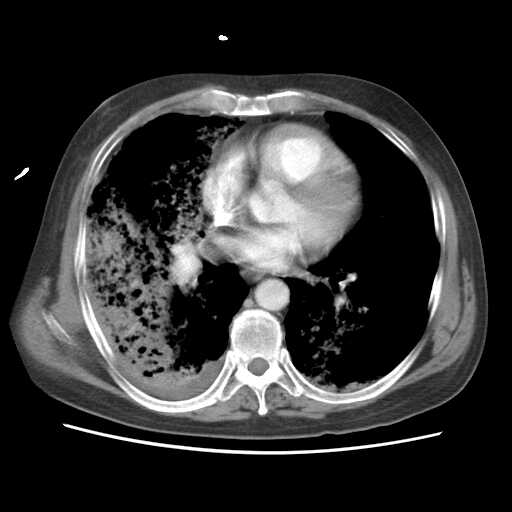

2008.8.17ct

病变从8.11-8.17明显改变,增多,以蜂窝状改变为主,类蜂窝肺,似弥漫性肺泡癌,但是病变进展太快,不符合弥漫性细支气管肺泡癌。因此考虑为特殊微生物感染,多以霉菌类常见,建议细菌微生物学检查。

疑点二:影象表现怪异,大片阴影内见多发筛孔征,如何解释.

结合临床慢支炎肺气肿,肺心病病史,三次胸片观察可见病情发展变化迅速,病情凶险,考虑多重感染伴ards.